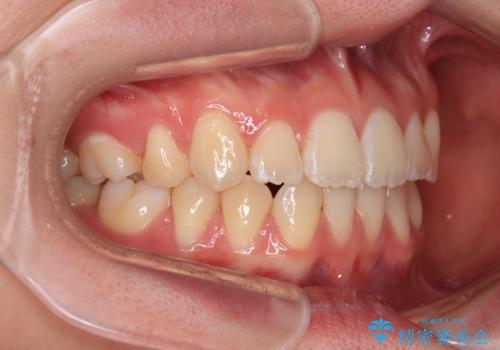

前歯が2本ない ワイヤー装置での抜歯矯正

- 下顎前歯欠損による隙間と、上顎前歯の突出感を気にして来院された患者様です。

横顔に出っ歯の印象はありませんでしたが、下顎のスペースと上下前歯の前後位置の大きなズレを改善するために、上顎左右の第一小臼歯2本を抜歯しすることとしました。

口元が引っ込みすぎないようにするために、上下ともに臼歯を前方に移動させる必要があり、インビザラインでは対応できないため、表側のワイヤー装置にて矯正治療を行うこととしました。